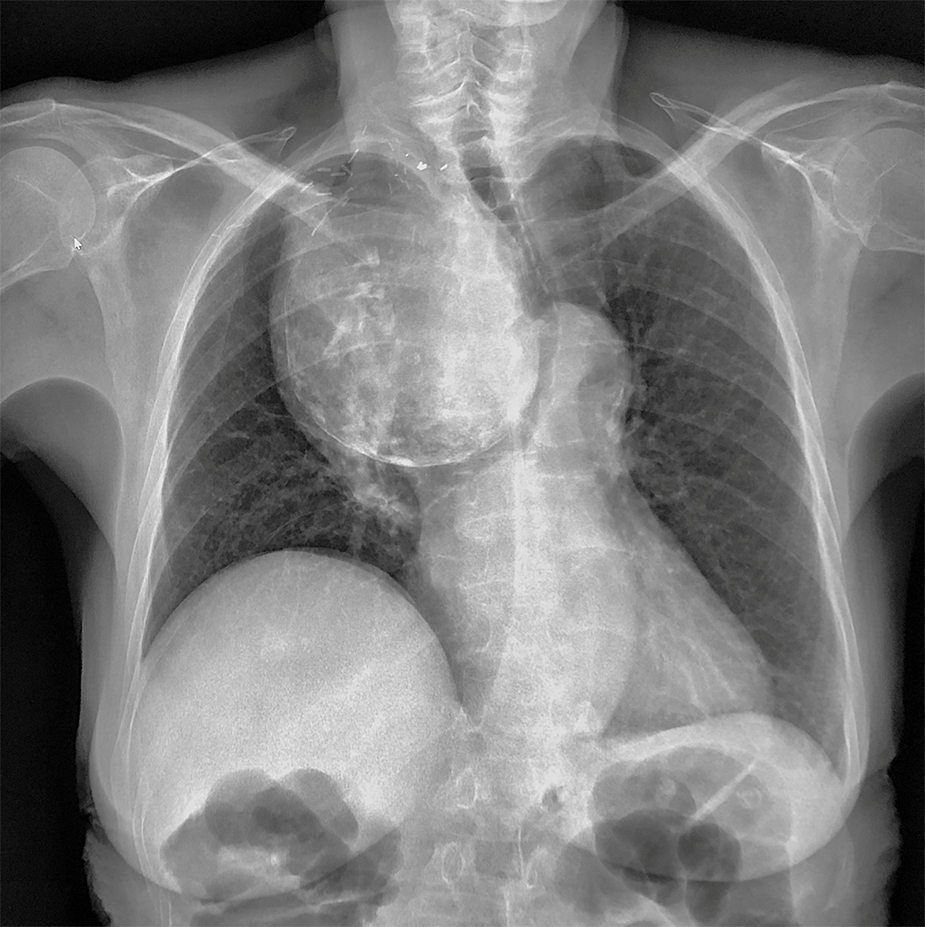

QUIZ N° 007

Patiente de 65 ans

QUEL EST VOTRE DIAGNOSTIC ?

A – GOITRE PLONGEANT

B – TERATOME MEDIASTINAL

C – THYMOME

D – LYMPHOME

E – ANEVRYSME EXCLU DU TABC